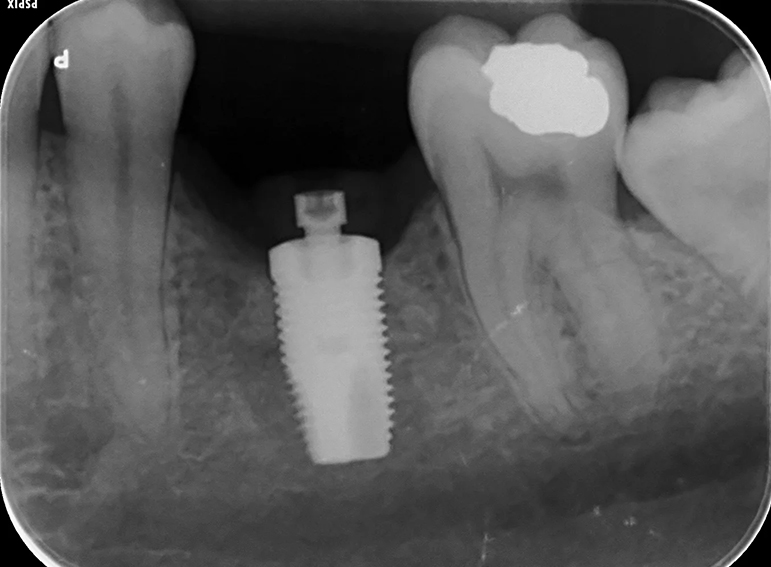

Implant to replace a molar with external cervical resorption.